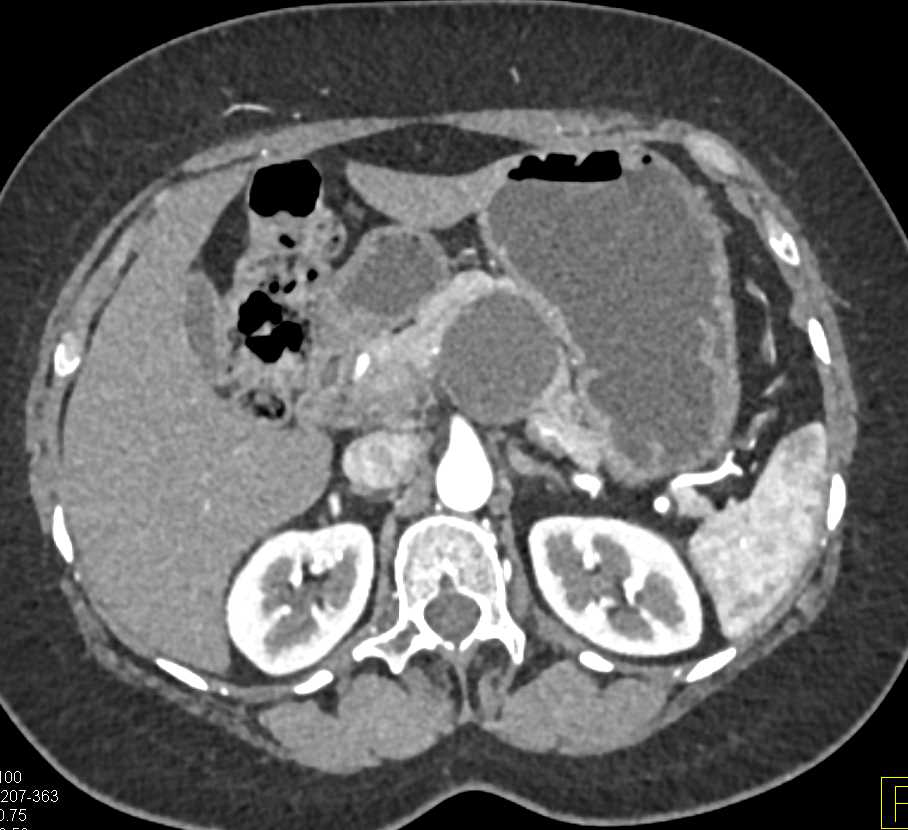

Adenocarcinoma Body of Pancreas with Cinematic Rendering